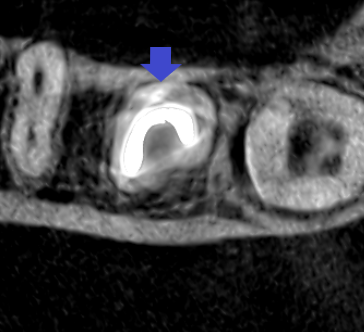

下顎第二大臼歯の根管充填の水平断のCT画像です。雨樋状に根管清掃・根管充填できています。根管充填時には、全ての痛みは消失していました。

精密根管治療6カ月後の経過観察時の矢状断のCT画像です。青い矢印の先にある膿の影の縮小が認められます。膿がかなり大きかったので、歯槽骨の再生は時間がかかっています。

精密根管治療6カ月後の経過観察時の冠状断のCT画像です。青い矢印の先にあった膿の縮小が認められます。歯槽骨が再生し、下顎管の圧迫も無くなってきています。